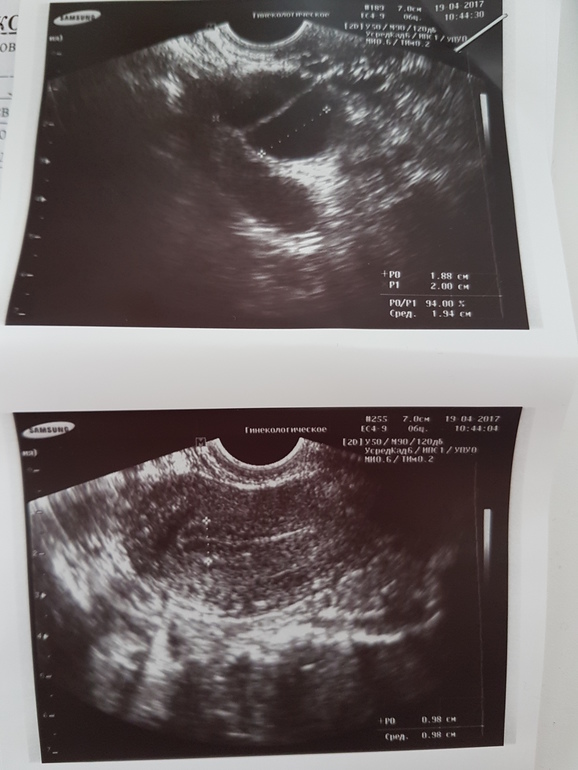

ФолликулометрияВсем привет.Позавчера была на фолликулометрии,два дф 18 и 20 мм.Сегодня попала к другому узисту,один фолликул 16 мм,почему так могло произойти?И второе-мне сказали,что эндометрий у меня отличается от нормального,типа,там такая "капелька" яркая должна быть,а у меня "еле нашли эту капельку",говорит,эндометриоз возможно.В интернете ничего не нашла по поводу яркости эндика на узи,это действительно так? К своему врачу попаду только на следующей неделе.

приблизительно на 14 день цикла когда у меня смотрели эндометрий, врач мне показывала, что типа вот он такой светленький плотный это хорошо. Что в этом хорошего я не поняла))) По цвету резко отличался, был такой светло серый. В конце (на дне матки) было такое утолщение... действительно похожее на капельку. После приема дюфастона но до М цвет поменялся и стал чуть более светлее цвета матки. Трудно различимым. А у вас на узи то что отмечено прям совсем темное... Сходили бы правда к другому узисту.

Толщина 9.9 мм,14 дц.

Она именно имела ввиду,что он темный,а не яркий,почти белый.Для сравнения показала мне фото нормы и того,что у меня

При этом, она пишет, что структура эндометрия однородная. Вы первый цикл делаете такое узи? Хотя бы, чтобы сравнить. Я сейчас не дома, но приду домой и посмотрю все свои снимки. Это только в последнее время я хожу к одному узисту, а до этого ходила к разным и аппараты разные. Может дело в аппарате?... границы эндометрия четко видно, но на фото он как будто не однородный, но она же пишет однородный. Поэтому даже не знаю, являются ли эти темные пятна действительно чем-то нехорошим.